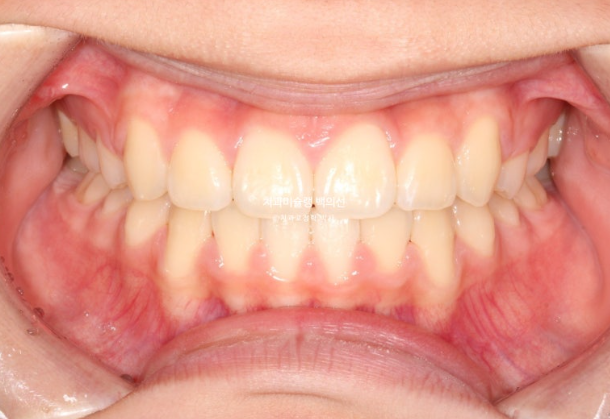

이제 전 후 비교 보겠습니다.

23.02~25.05

총 치료기간은 2년 3개월입니다.

코와 인중이 맞아진 상악 중심선

2mm의 어긋남이 해소가 되어 맞아진 상악과 하악 치아중심선

적절한 입동굴로 아담해진 치열

완만한 U자형의 스마일라인

미소가 훨씬 정돈되고 깔끔한 느낌이 듭니다.

뻗치치도 옥니처럼 뒤로 너무 들어가지도 않은 적절한 앞니 각도

입술 돌출 역시 과하지 않게 입술 볼륨감을 유지한채 적당히 들어갔습니다.

결과에서 보듯 작은어금니 4개 발치는 불필요했습니다.

윗니돌출이 해소가 되면서 입술이 편하게 다물립니다.

치료당시 아직 중학생이라 성장에 의해 아래턱이 조금 성장했습니다.